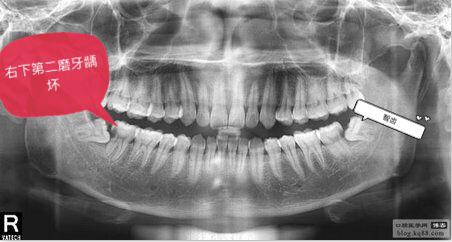

智齿的阻生或错位易使食物残渣嵌塞在第二磨牙与智齿的牙间和牙周缝隙中,很不容易清除,常发生龋齿。

据调查,下颌第二磨牙牙颈部平均龋患率为16.4%,不同年龄阶段龋患率有显著不同,20岁时仅为3.7%,50岁则高达27%。可见,拔除阻生或错位智齿是预防第二磨牙龋坏的关键。